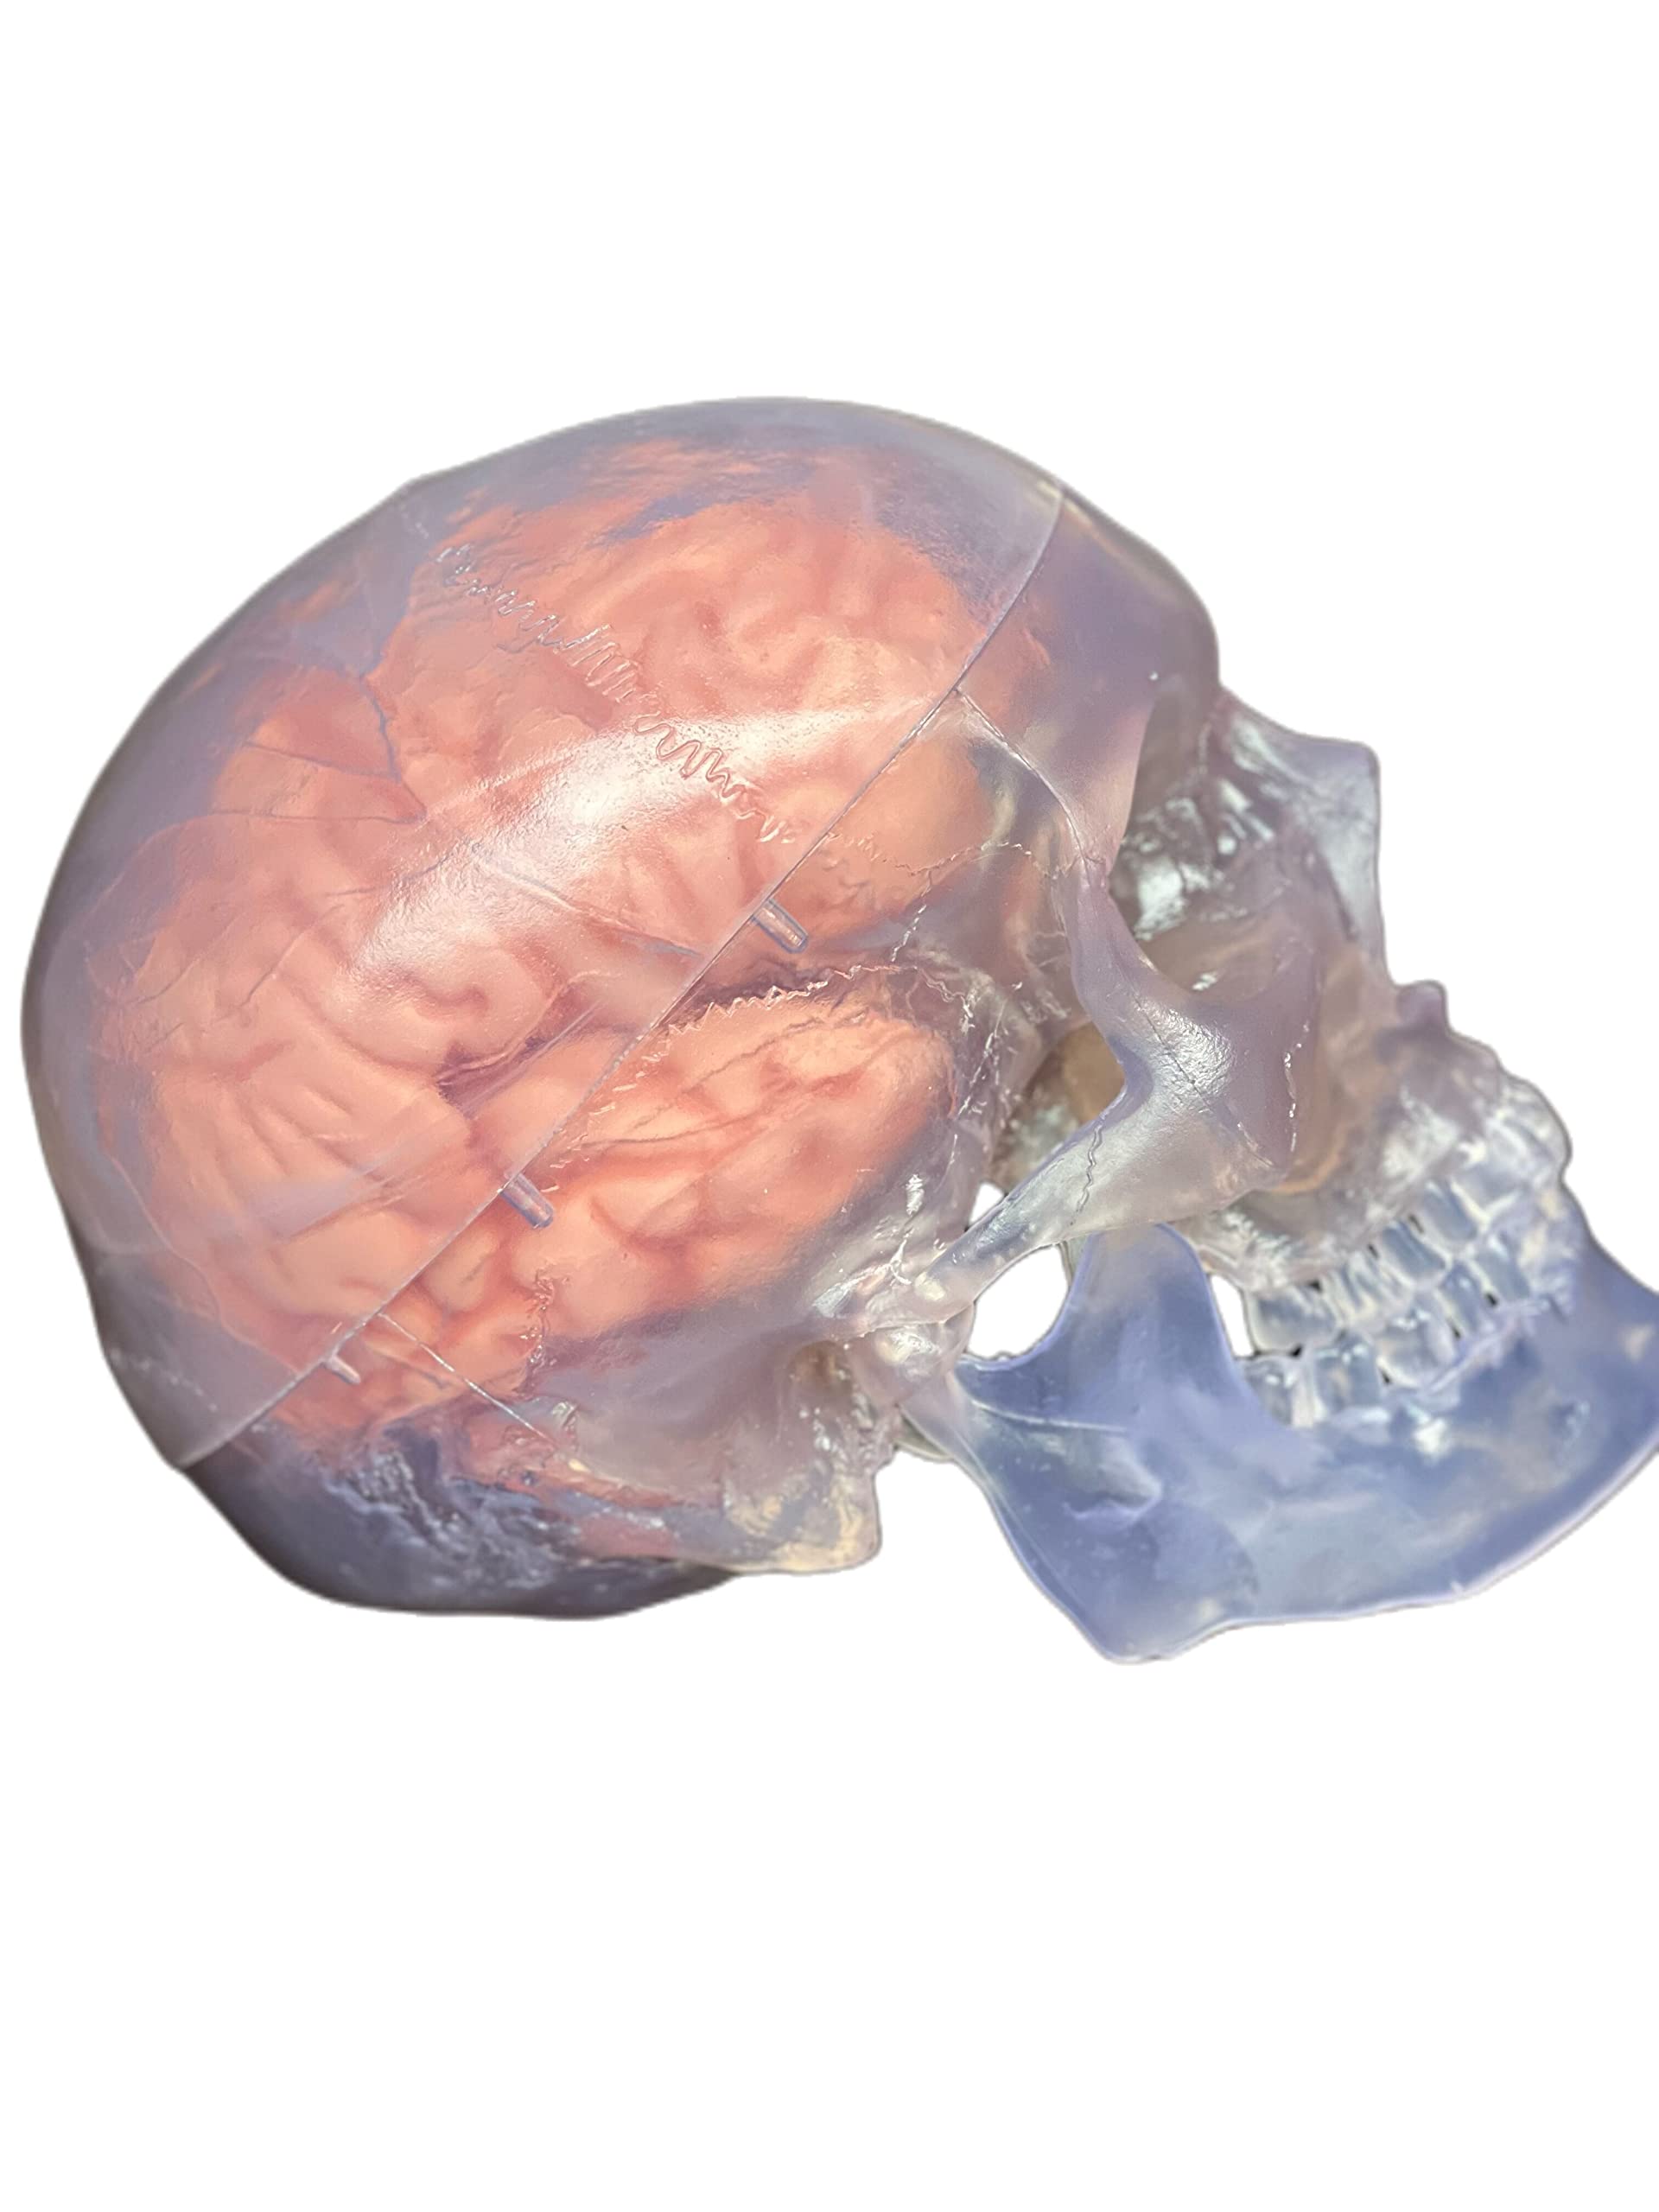

This model is cast from a high-quality original specimen. The classic skull is medically detailed in structure. It has highly accurate representation of the fissures, foramina, processes, sutures etc. Skull is 3-part: Skull Cap, Base of Skull and Mandible. The mandible is articulated on springs to demonstrate natural movements. Use this unique transparent replica of the human skull to study internal structures that otherwise are visible only through x-ray images. Brain separates into 8 parts: frontal and parietal lobes (2), temporal and occipital lobes (2), medulla (2), cerebellum (2). Structures are shown in great detail with about 30 features marked with numbers. Number key is provided. A great addition to any educational collection. Size: Life size Measurement: 22X13X17cm Weight: 2 kgs Material: high quality PVC

- The skull is 3-part: Calvaria, Base of Skull, and Mandible.